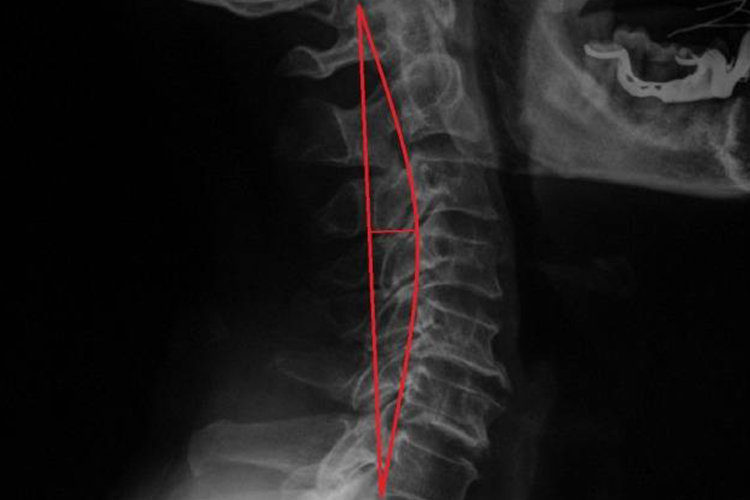

正常人的颈椎呈轻微前凸,主要是由于颈4、颈5椎间盘前厚后薄,造成颈椎中段有向前突出的弧度。颈椎间隙纤维环是完整形态,髓核没有膨胀或者突出。